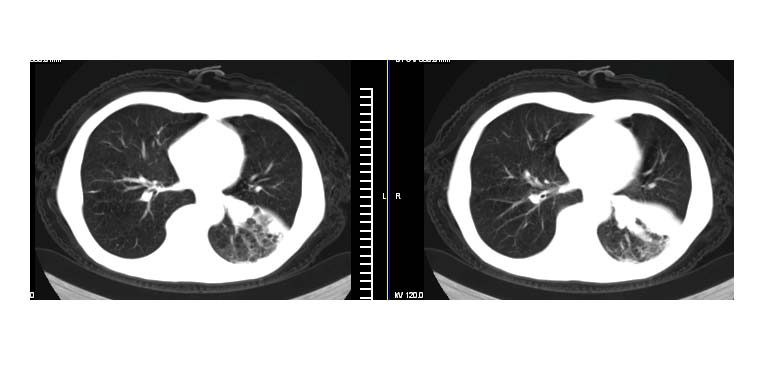

标题: CT11019:男性,66岁。发烧5-6天。治疗后无明显好转。 [打印本页]

标题: CT11019:男性,66岁。发烧5-6天。治疗后无明显好转。

左侧胸廓偏小,左下梭形高密度影,考虑阻塞性肺炎.

斜肋积液

斜裂积液,炎症

明明是斜裂胸膜积液,为何都考虑阻塞性肺炎、肺不张(边缘内凹,而本例是外凸)。